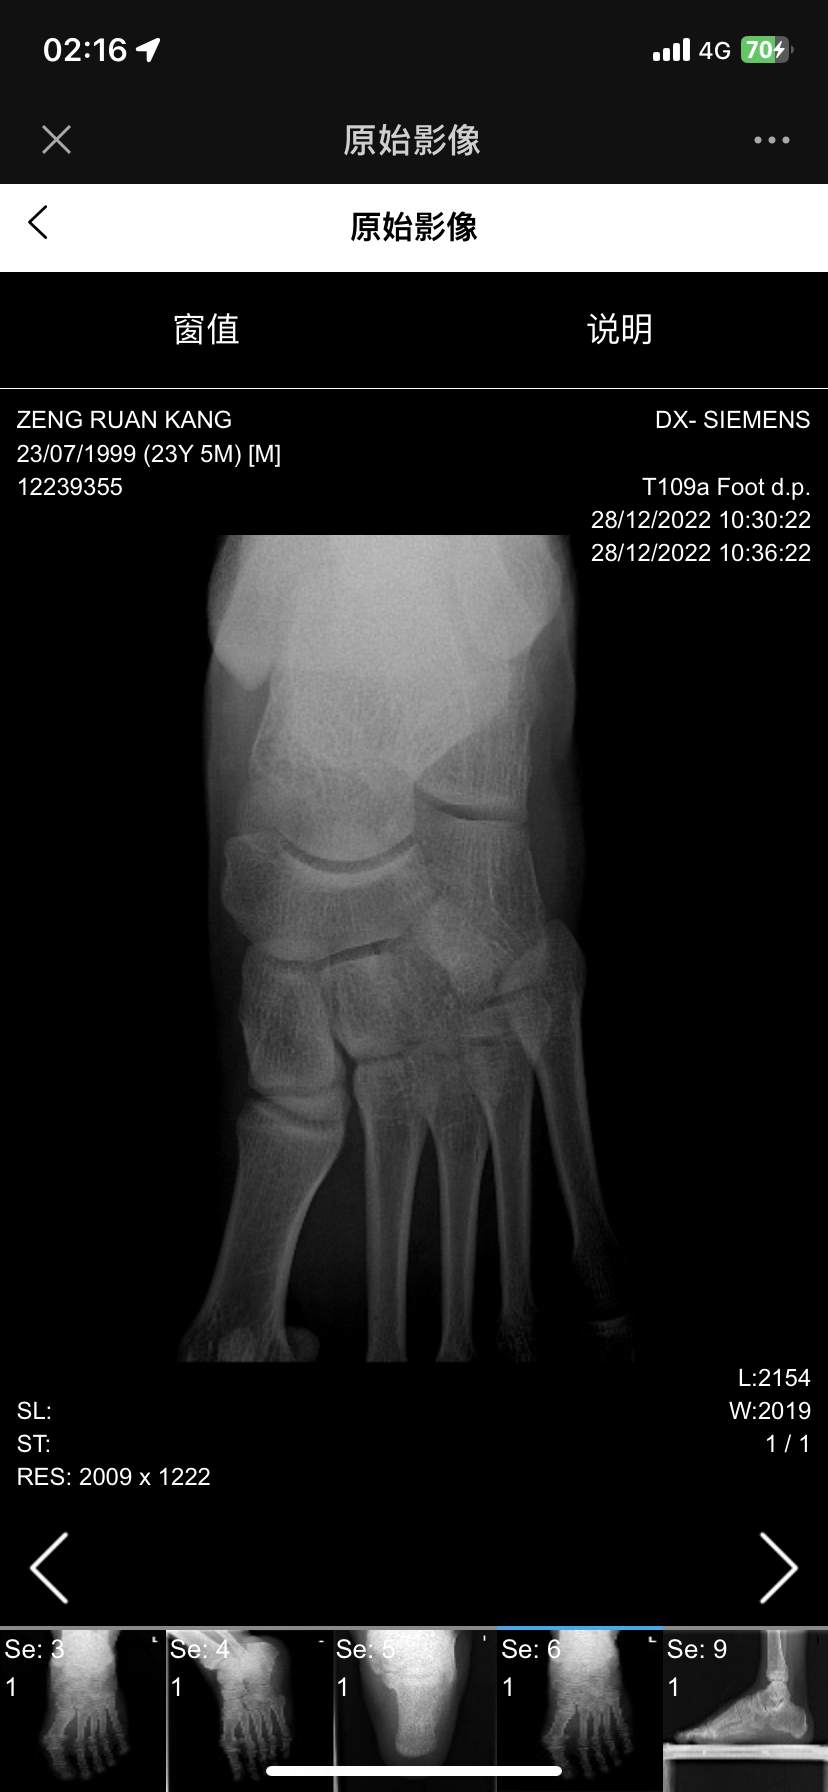

扭伤后组底外侧跟骰关节处疼痛五年,骰骨综合征?

患者五年前跖屈内翻扭伤,痊愈后才注意到足底外侧骰骨处疼痛,行走时尤甚,随着活动增加而加重,这几年找了很多足踝大夫都看不出来,因为b超磁共振和x光没有显示任何结构问题,也没有炎症水肿的表现,活动度也基本正常,内外翻跖屈背曲无痛,尝试过药物,封闭,针刀,冲击波等效果均不佳,因疼痛影响生活轻度抑郁,老师们考虑这是什么病?